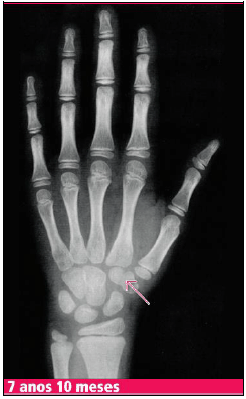

Paciente, sexo feminino, 5 anos e 3 meses, comparece à consulta por aparecimento de broto mamário. Mãe percebeu que nos últimos três meses houve crescimento de mamas. Refere que na escola é a criança mais alta da turma. Foi realizado Raio X de mãos e punhos para correlação da idade óssea com idade cronológica, com o seguinte resultado:

Qual o marco anatômico indicado para a identificação da idade óssea apresentada?